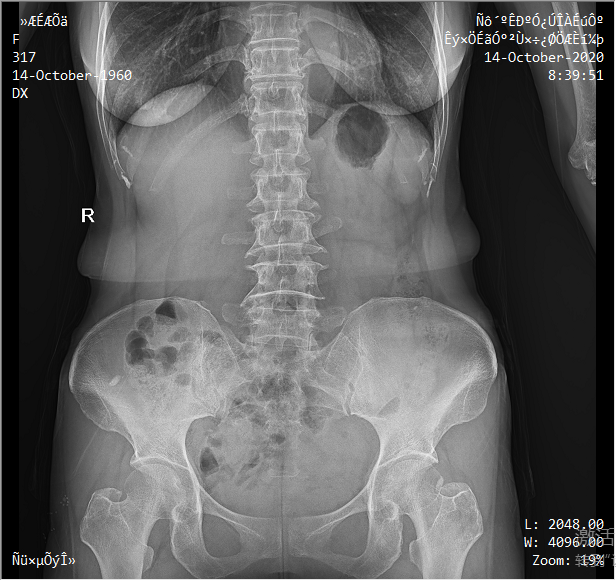

采用靈活的懸吊式機(jī)架設(shè)計,配置電動升降攝影床/移動床與高品質(zhì)平板探測器,實現(xiàn)圖像與擺位的有機(jī)統(tǒng)一,可應(yīng)用于DR攝影多種臨床X線檢查領(lǐng)域。

醫(yī)生選擇需要拍攝的部位,自動生成擺位示意圖像,引導(dǎo)病人快速準(zhǔn)確的完成擺位。

依據(jù)臨床圖像庫自動進(jìn)行圖像后處理,呈現(xiàn)效果佳。